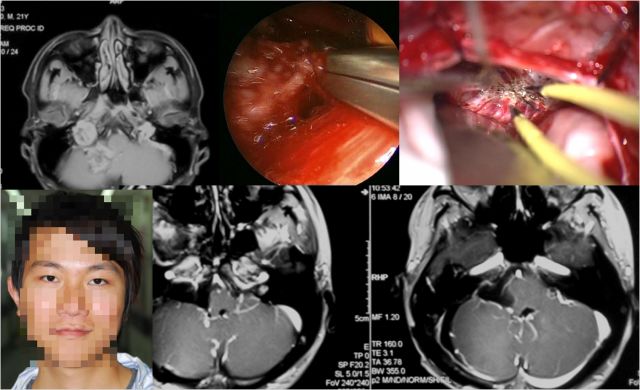

鲍遇海教授:前庭神经鞘瘤的膜及包膜的手术 意义

坐位听神经瘤切除术视频(摘自鲍教授上述讲课)

鲍遇海教授:坐位听神经瘤切除术

听神经瘤

手术体位个性化选择